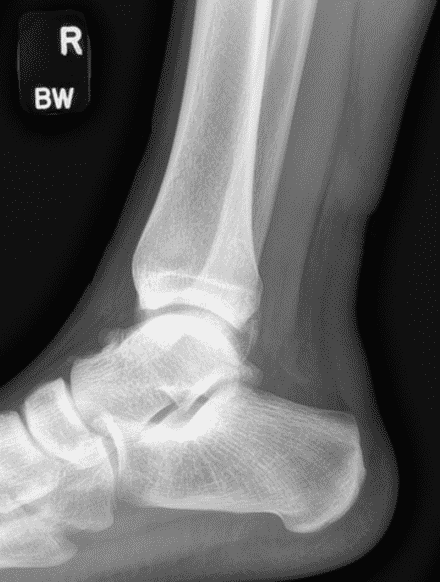

A 22 year-old male college football player presents with a “pop” and pain posterior to the right ankle during practice 1 week prior. He is unable to bear weight. Lateral radiograph (1A), sagittal fat-suppressed T2-weighted (1B), sagittal T1-weighted (1C), and transverse fat-suppressed T2-weighted images are provided. What is your diagnosis? What MRI findings affect clinical management decisions?

Figure 2: Complete Achilles tendon rupture. (2A) The lateral radiograph shows a thick and indistinct proximal Achilles tendon contour (arrows). (2B) A fat-suppressed T2-weighted image shows complete rupture of the tendon with a fluid-filled gap (yellow arrow) measuring 1.5 cm in length, located 10 cm cranial to the tendon insertion (blue arrow) and just distal to the edematous myotendinous junction (red arrow). The tear is superimposed on diffuse tendinosis. (2C) A sagittal T1-weighted image confirms the diffuse tendinosis. Fluid extends anteriorly into Kager’s fat pad (arrow) suggesting disruption of the anterior paratenon. (2D) A transverse fat-suppressed T2-weighted image through the proximal tendon shows no intact fibers (arrow), confirming the full-thickness rupture.

Acute, complete Achilles tendon rupture just distal to the myotendinous junction, superimposed on diffuse tendinosis.